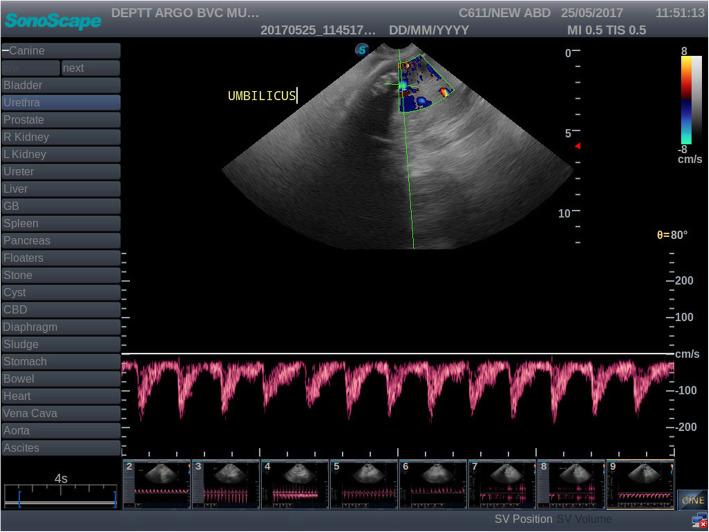

Ultrasonographic monitoring of the pregnant bitch is an established routine in many veterinary clinics. In order to better assess foetal health and avoid pregnancy losses, Doppler ultrasonographic evaluation of the pregnant uterus is the need of the day. Investigations on the dynamics of maternal and foetal blood flow using Doppler ultrasound have been conducted in multiple species recently and it is invisaged that it would be a reliable diagnostic tool in future in monitoring pregnancy. The present study was designed to compare Doppler parameters systolic peak velocity (SPV), end diastolic velocity (EDV), pulsatility index (PI) and resistivity index (RI) of the uteroplacental (UPA) and umbilical arteries (UA) measured during 40 to 50 and 51 to 60 days in normal gestation and threatened abortion in canines.

In total 40 pregnant bitches with known history of breeding; irrespective of age and parity belonging to different breeds were classified into normal gestation (NG) and threatened abortion (TA). Bitches with the history of greenish black discharge or expulsion of one foetus were included in the abortion group and bitches with no such symptoms were included in the normal gestation group. End diastolic velocity of uteroplacental vessels decreased while PI and RI increased significantly with decrease in body weight in threatened abortion cases during 40 to 50 and 51 to 60 days of gestation in canines. Systolic peak velocity and EDV of umbilical arteries increased while PI decreased significantly with decrease in body weight during 40 to 50 days of gestation in canine threatened abortions.

Doppler evaluation of uteroplacental and umbilical arteries is recommended as a diagnostic tool to monitor high risk pregnancy during 40 to 50 and 51 to 60 days of gestation in canines.